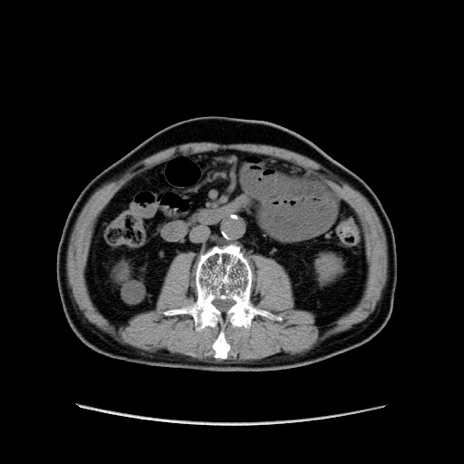

症例24(横断像)

【症例】80歳代男性

【主訴】左側腹部痛、嘔吐

【現病歴】本日早朝より左腹部に痛みあり。昼頃嘔吐認めたため、救急要請。

【既往歴】直腸癌(Mile手術)、胆摘

【身体所見】意識清明、BT 35.9℃、BP 221/93mmHg、SpO2 97%(RA) 、腹部:左ストーマ周囲に限局性の腹部膨隆あり。 膨隆部自発痛・圧痛あり・軟。

【データ】WBC 7700、CRP 0.09